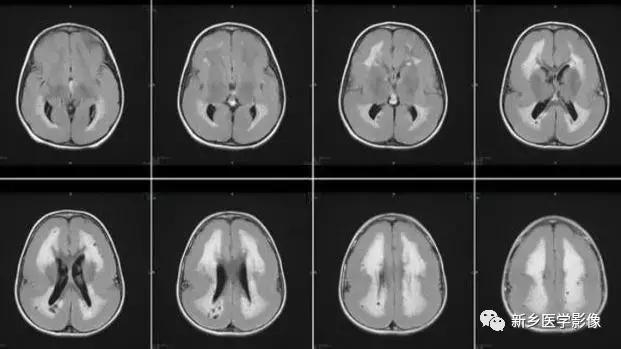

1.交通性脑积水

又称脑室外梗阻性脑积水,是由四脑室出口以后脑脊液循环通路障碍所致的脑积水。常位于蛛网膜下腔,以基底池最常见。主要原因包括脑膜炎、蛛网膜下腔出血、脑膜转移、外伤、静脉窦血栓、颅脑手术后和脑脊液吸收功能障碍等。临床表现主要由颅压增高所引起. 可表现有头痛、呕吐、复视和视乳头水肿等。交通性脑积水时.第四脑室扩大通常出现较晚,故早期时,可仅表现有侧脑室和三脑室扩大。主要应与导水管狭窄之梗阻性脑积水区别。MR矢状位T1加权图直接观察导水管有无狭窄的最好方法。另外需要与普遍性脑萎缩区别,脑萎缩时沟脑裂增宽,而脑积水时脑沟变窄消失或正常。另外.三脑室扩大不明显脑室扩大比较明显。脑萎缩时三脑室扩大较明显。到晚期,交通性脑积水出现整个脑室系统普遍扩大而脑沟正常或变窄消失。

2.正常压力性脑积水

实际上是交通性脑积水的一种特殊类型.又称隐匿性脑积水、低位性脑积水或慢*交性**通性脑积水。脑脊液压力正常的原因可能是由①脑脊液代偿性分泌减少,而吸收加强,使脑脊液压力处于相对正常状态;②脑脊液经室管膜吸收。使脑脊液压力保持止常;③脑实质的张力降低。正常压力性脑积水可能由隐匿性蛛网膜下腔出血或感染所致.也可能继发于其他颅脑疾病。包括蛛网膜下腔出血、脑外伤、炎症、颅脑手术后粘连等。正常压力性脑积水常见于50岁以后。临床表现实际上是慢*交性**通性脑积水的表现加上脑萎缩的表现,其典型临床表现为痴呆、步态异常和二便*禁失**,并呈进行性加重。少数病例还有肢体和短暂意识障碍。CT和MR检查表现为普遍性脑室扩大,但脑沟并不变窄或消失。或表现有脑沟脑裂增宽,与脑萎缩鉴别很困难。正常压力性脑积水也可仅表现有脑萎缩,而没有脑室扩大,所以,临床症状典型时,仅有脑萎缩表现并不能除外正常压力性脑积水的诊断